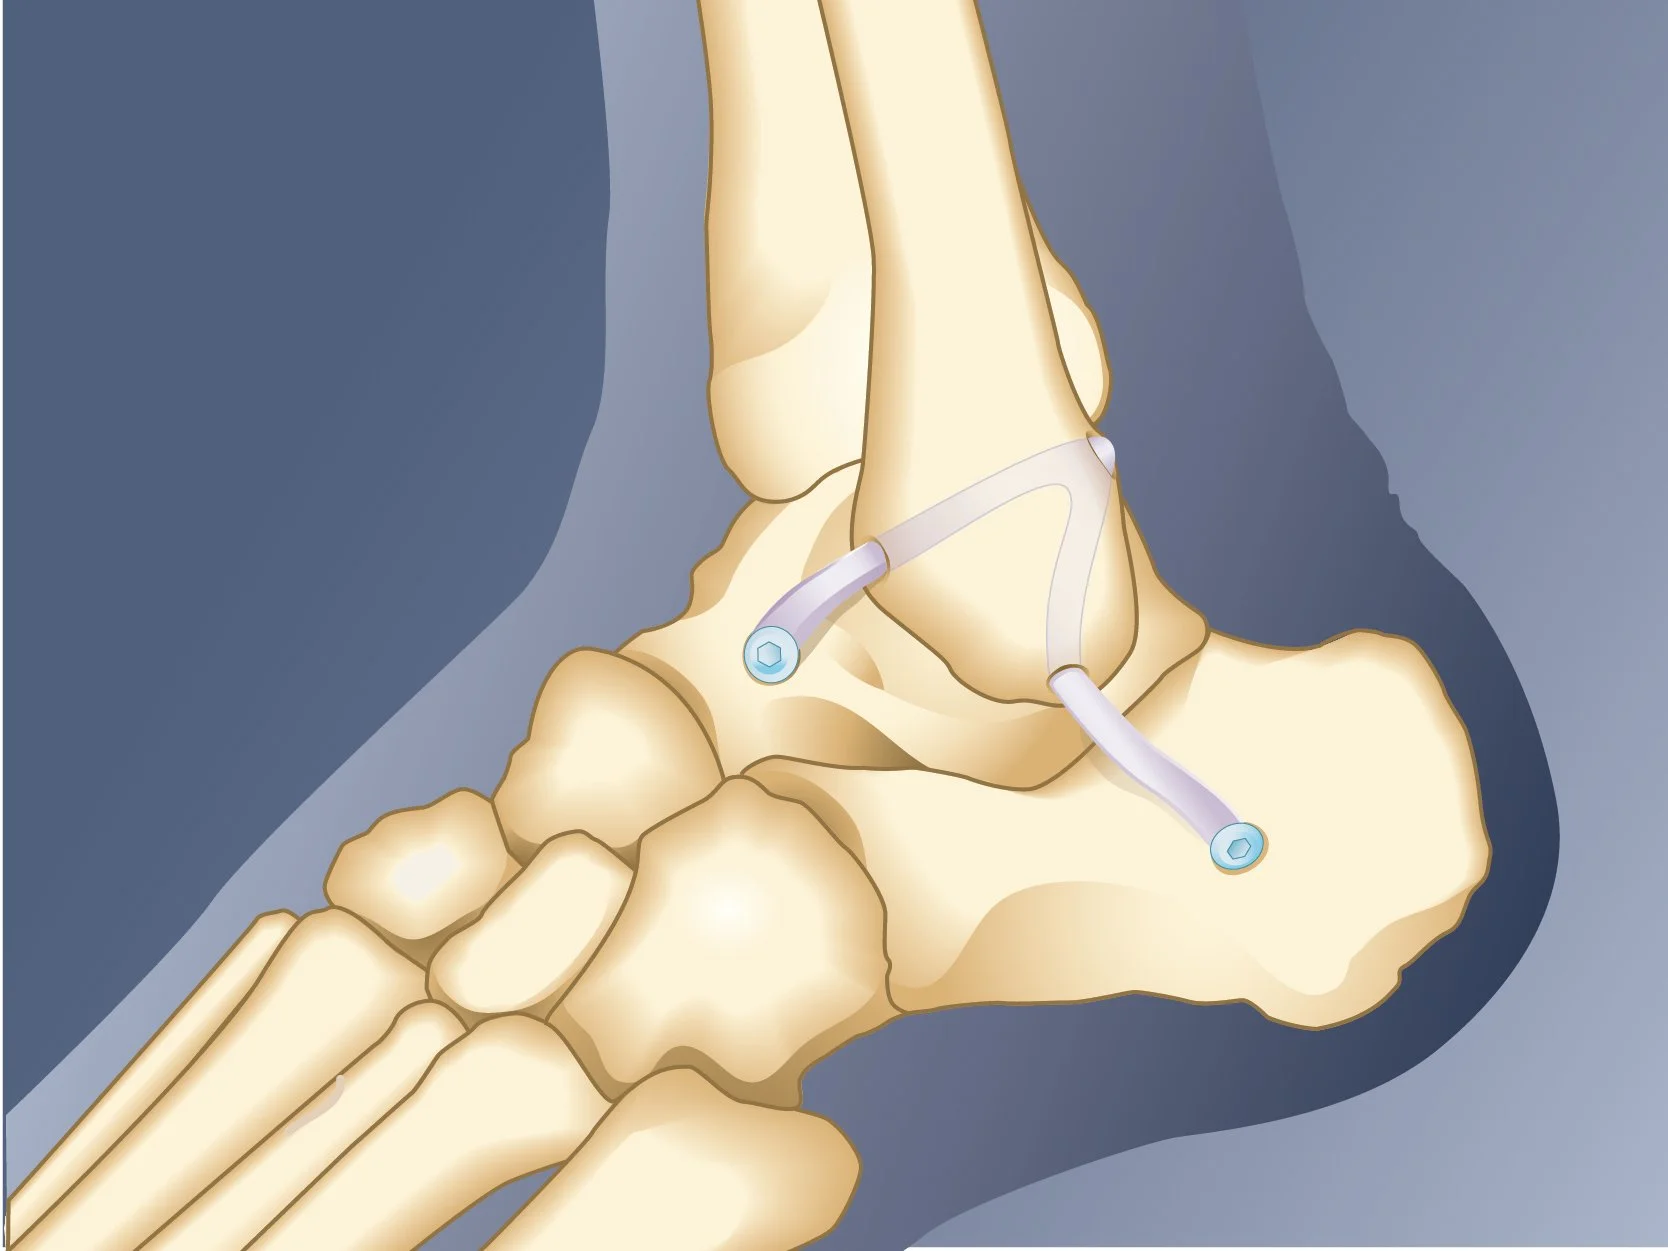

Surgical illustrations visually depict operative techniques, surgical anatomy, and complex procedures. They are created with high anatomical accuracy and serve as a visual bridge between complex surgical knowledge and learners, clinicians, or patients.